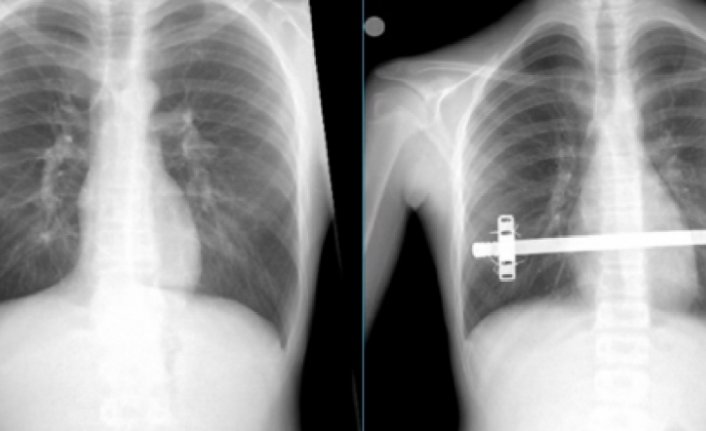

TRABZON (AA) - Trabzon'da, halk arasında "kunduracı göğsü" olarak bilinen Pektus Ekscavatum hastalığı ile mücadele eden Hamza Suiçmez, 2 saat süren ameliyatın ardından sağlığına kavuştu.

Suiçmez'e, yapılan tetkikler neticesinde halk arasında "kunduracı göğsü" olarak da bilinen Pektus Ekscavatum hastalığı tanısı konuldu.

Erken yorulma ve çarpıntı şikayetlerinin, içeri doğru basık olan iman tahtasının kalp üzerine baskı yapmasından kaynaklandığı anlaşılan hasta, KTÜ Farabi Hastanesi Başhekimi ve Göğüs Cerrahisi Anabilim Dalı Başkanı Prof. Dr. Celal Tekinbaş ve ekibi tarafından ameliyat edildi.

"Kapalı kunduracı göğsü ameliyatı (NUSS)" uygulanmasının ardından sağlığına kavuşan Suiçmez, şikayetlerinin artık olmadığını ve en önemlisi de kendisini daha özgüvenli ve sosyal hissettiğini belirtti.